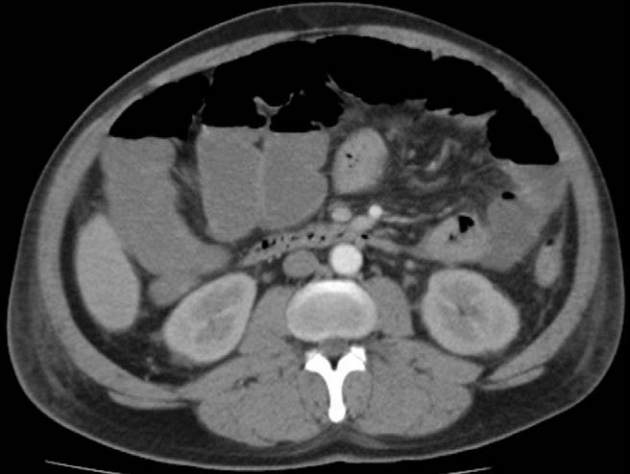

Abb. 3

Computertomographischer Befund einer Pneumatosis intestinalis einer terminalen

Ileumschlinge. Dünn- und Dickdarmileus.